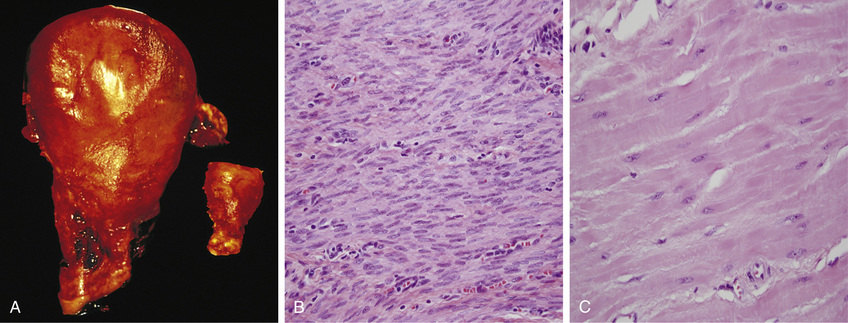

• An example of pathologic hypertrophy is the cardiac enlargement that occurs with hypertension or aortic valve disease (Fig. 2.21). The differences between normal, adapted, and irreversibly injured cells are illustrated by the responses of the heart to different types of stress. Myocardium subjected to a persistently increased workload, as in hypertension or with a narrowed (stenotic) valve, adapts by undergoing hypertrophy to generate the required higher contractile force. If, on the other hand, the myocardium is subjected to reduced blood flow (ischemia) due to an occluded coronary artery, the muscle cells may undergo injury.